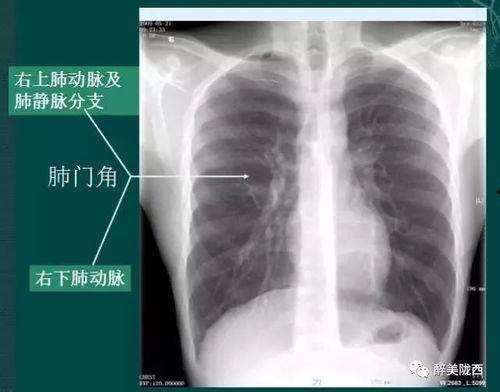

首先,得先弄清楚什么是胸片。胸片,顾名思义,就是通过X射线对人体胸部进行拍摄的一种医学影像检查。它能够清晰地显示出心脏、肺部、纵隔等器官的结构和形态,对于诊断各种胸部疾病有着至关重要的作用。